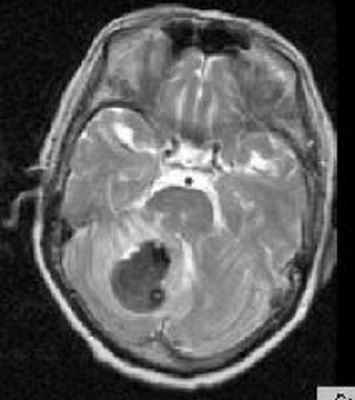

МРТ головного мозга. Аксиальная Т2-взвешенная МРТ. Кровоизлияние в мозжечок.

Субдуральная гематома обычно возникает вследствие разрыва вен. Причины субдуральной гематомы – травма, антикоагулянтная терапия, резкая декомпрессия при шунтировании желудочков по поводу гидроцефалии. Очень редко встречаются субдуральные гематомы при разрыве аневризм и АВМ. Клинические проявления связаны смасс-эффектом. Частота субдуральных гематом составляет около 1 случая на 10 тысяч населения. Располагаются субдуральные гематомы по конвекситальной поверхности, изредка, вдоль межполушарной щели и намёта, в области задней черепной ямки. Может быть сочетание субдуральной гематомы с кровоизлиянием в соседние участки мозга. прогноз в этих случаях неблагоприятный. Отображение гематомы на КТ и МРТ зависит от их давности. Субдуральные гематомы имеют форму серпа.

МРТ головного мозга. Аксиальная Т2-взвешенная МРТ. Подострая субдуральная гематома.